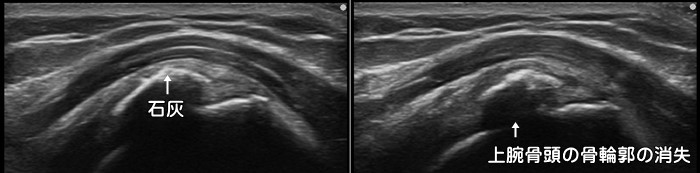

石灰沈着性腱板炎

肩を真横へ上げていく外転動作での痛みが強いのが特徴です。急性型の場合は前日まで全く症状がなく、朝起きると激痛で肩が上がらなくなります。10日前後で痛みは消失しますが慢性型の場合は数年にわたって肩の痛みが続き、年のせいだと石灰沈着に気が付かない場合もあります。好発部位は肩の棘上筋・棘下筋と呼ばれる筋肉内ですが、石灰は体の至る所に沈着します。